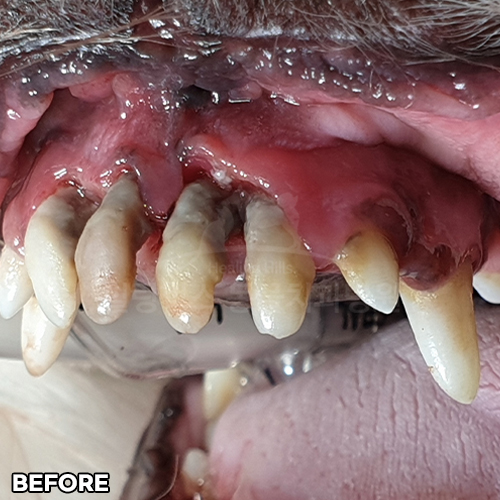

[심한 치주염 최대한 치아를 살리며 최소침습적발치]

샘플